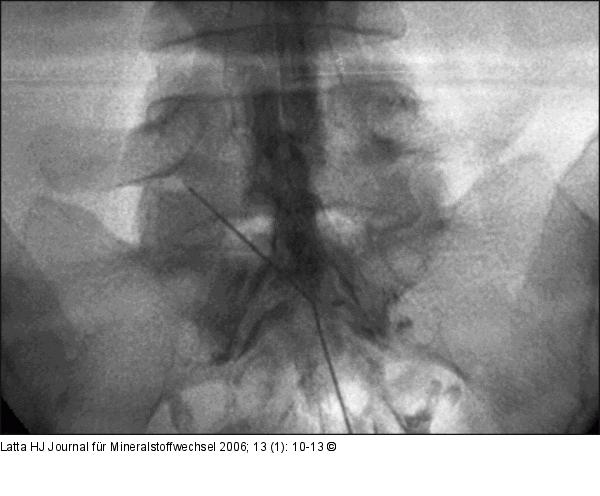

Abbildung 4: Hiatus sacralis - Epiduralkatheter Über den Hiatus sacralis eingeführter Epiduralkatheter nach Racz bei L5/S1 links. |

Über den Hiatus sacralis eingeführter Epiduralkatheter nach Racz bei L5/S1 links. |